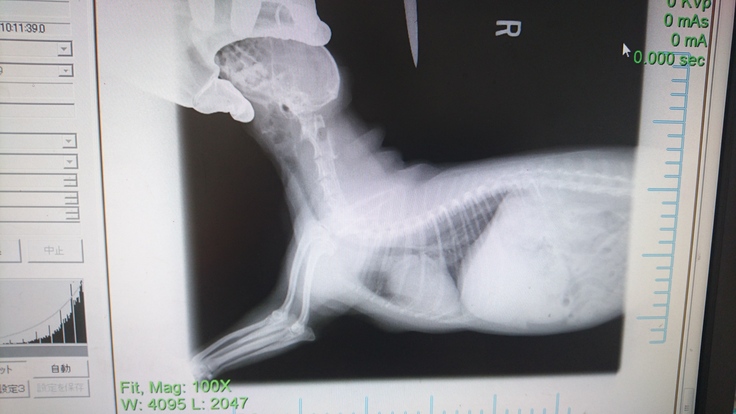

診断の結果は気管虚脱ということでした。

気管虚脱とは、空気の通り道である気管が途中で潰れてしまい、呼吸ができなくなってしまう病気です。

通院している病院にてレントゲンと血液検査を送り、アトム動物の先生に診ていただいたところグレード3ということでした。手術の日程や費用についてアトム動物病院に問い合わせたところ、手術から退院まで100万かかるということでした。